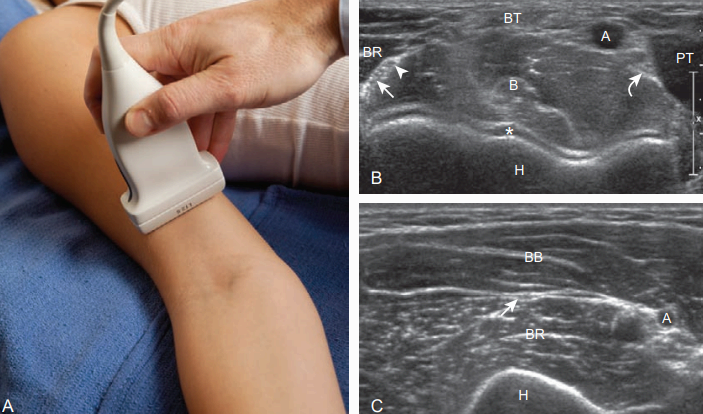

공동굽힘힘줄과 자곁인대의 앞쪽띠에 대한 검사를 마친 후, 곧바로 그 뒤에 있는 팔꿉굴 부위를 검사한다. 팔꿈치를 바깥쪽으로 돌린 상태에서 팔꿈치돌기의 뼈융기(bony protuberances)와 안쪽 위관절융기를 눈으로 확인하거나 만져본다. 탐촉자를 놓으면 특징적인 높은 에코와 소리그림자(acoustic shadowing)를 보이는 뼈 윤곽을 찾을 수 있다.

자신경은 낮은 에코의 굵은신경다발과 높은 에코의 결합조직으로 인해 벌집 모양으로 보인다. 그러나 팔꿉굴 부위의 정상 자신경은 전형적으로 높은 에코의 지방에 둘러싸인 낮은 에코의 구조물로 보이며, 노쪽손목굽힘근의 두 갈래와 그 위의 활꼴인대 사이에서 팔꿉굴의 아래쪽으로 주행하는 것을 확인할 수 있다. 탐촉자를 90도 회전하면 자신경을 세로로 검사할 수 있다. 팔꿉굴 부위의 병변을 역동적으로 검사하는 것이 중요하다. 다시 탐촉자를 가로면으로 위치시키고, 안쪽 위관절융기 위에 고정시킨 후 환자의 팔꿈치를 능동적으로 구부리게 한다. 이때 팔꿈치돌기는 영상에서 사라지고 낮은 에코의 위 팔세 갈래근이 공간을 대치한다. 정상적으로 자신경은 위관절융기의 꼭지(apex)를 향해 움직이지만 위관절융기보다 앞쪽으로 이동하면 안 된다. 위관절융기보다 앞쪽으로 이동된 신경은 팔꿈치를 펴면 정상 위치로 되돌아오면서 퉁김(snap)을 보인다. 역동적 검사를 시행할 때는 자신경의 비정상적 이동이 방해되지 않도록 탐촉자로 지나친 압력을 검사 부위에 가하지 않아야 하며, 적절하게 압력을 조정함으로써 이러한 문제를 피할 수 있다. 자신경어긋남(ulnar nerve dislocation)은 증상이 없는 사람의 약 20%에서 나타나며, 이를 진단할 때는 자신경의 비정상적 형태와 증상을 고려하여 판단하는 것이 중요하다. 위팔세 갈래근 퉁김 증후 근(snapping triceps syndrome)은 팔꿈치를 굽힐 때 위 팔세 갈래근의 안쪽갈래와 자신경이 위팔뼈의 안쪽 위관절융기 위로 어긋나며, 고립성 자신경 어긋남(isolated ulnar nerve dislocation)과 감별해야 한다.